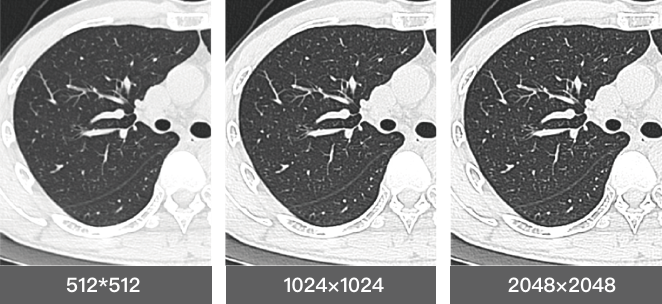

Wide detector expands single-rotation coverage, shortens exam time, reduces motion artifacts, decreases radiation dose, and saves tube exposure time while effectively lowering operating costs